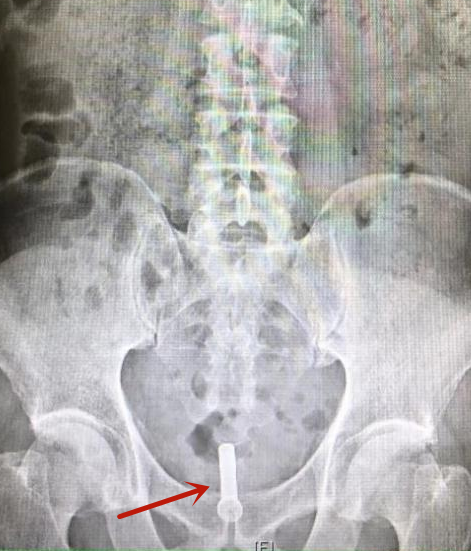

红色箭头处为支架植入位置

另一位前列腺增生患者,4月前在山东当地医院准备行前列腺激光术前突发急性心梗,行介入心脏冠脉支架留置术并应用抗凝药物后,反复出现尿潴留,只能长期留置尿管,严重影响日常生活质量,心理负担较重。经推荐来到清华长庚,胡卫国和主治医师付猛团队在局部麻醉下,仅用时20分钟便为他行前列腺金属支架植入术,患者回到病房即可自行顺畅排尿,“终于卸下了一个重重的包袱!”患者说道。